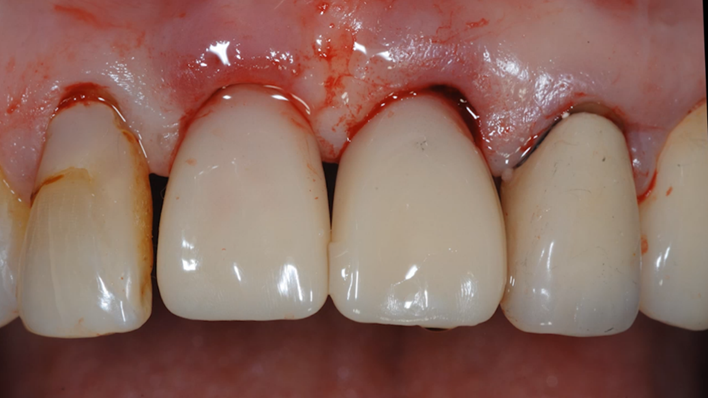

Clinical case: Extraction, immediate placement & loading using

R2GATE solution in aesthetic zone

- Courtesy of Dr. Jong-Cheol Kim, Korea-